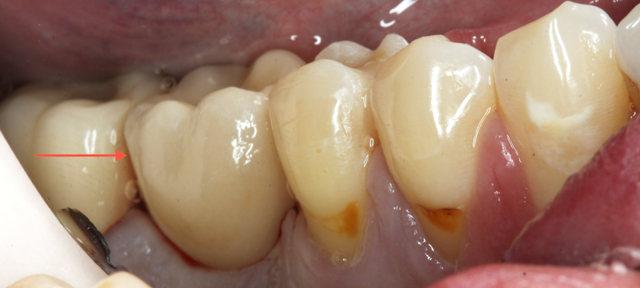

The patient, a healthy 38-year-old male with an unremarkable medical history, presented with a non-restorable tooth #19.

The tooth had a vertical root fracture and recurrent decay. The patient was given an option for an implant at site #19 or a fixed bridge from teeth #18-20. The patient elected to have the tooth extracted and an implant placed immediately at the time of extraction. The implant placement was planned using a CBCT scan and Galaxis software.